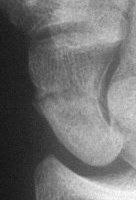

Case 5. Another,same bidirectional technique. Here, I ran the second screw too close to the first, and may have flattened the leading threads - not

ideal. The preop status:

Click for larger image